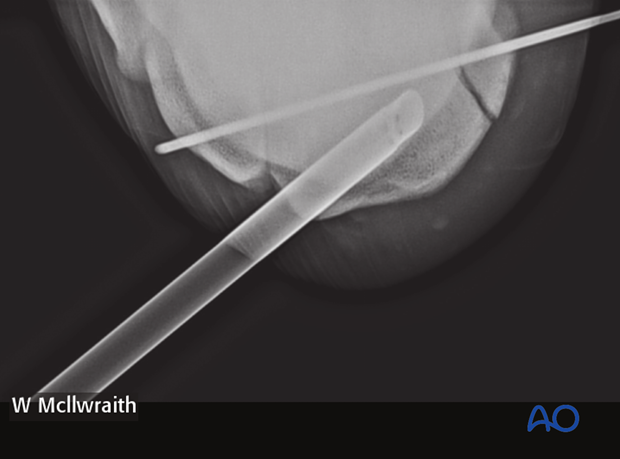

An 18 gauge spinal needle is inserted percutaneously under arthroscopic visualization so that it passes in the center of the fracture portion half way between the fracture line and the junction of the second and third carpal bones. The needle is passed across the joint and embedded in the soft tissue of the lateral joint capsule.

This needle is the critical directional guide for implant placement.

Once the spinal needle has been placed, an additional18 gauge needle is inserted into the carpometacarpal joint directly below the initial needle placed.

Based on the radiographs a stab incision is made over the medial aspect of the third carpal bone half way between the spinal needle and the needle in the carpometacarpal joint using the spinal needle as a guide for the dorso-palmar positioning.

A 3.5 mm glide hole is drilled across the fragment using the spinal needle as a guide to place the glide hole approximately perpendicular to the sagittal fracture line.

The drill depth and direction can be verified using an intraoperative radiographic view.